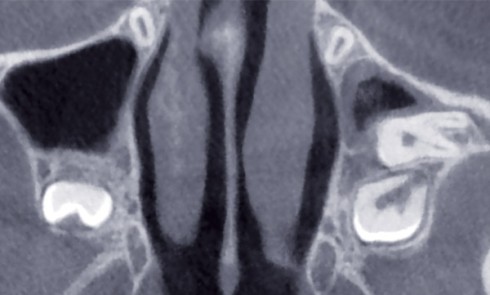

Le positionnement tridimensionnel d’un implant n’est pas uniquement conditionné par le volume osseux disponible et les structures anatomiques bordant l’édentement,...